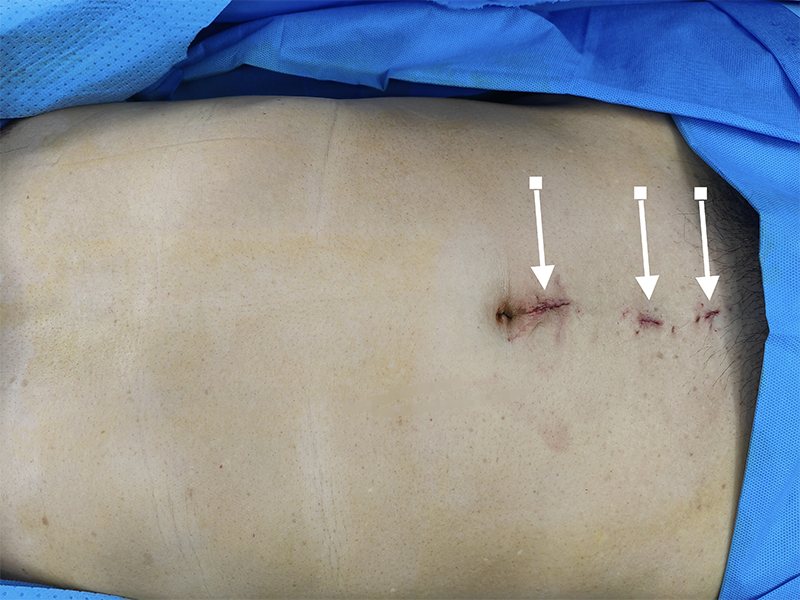

腹腔镜手术是目前腹股沟疝的主要治疗术式,可减轻对机体造成的创伤,加快术后康复速度。在腹部手术中,不仅要考虑康复效果,也要兼顾腹部伤口疤痕问题,而疝气微创手术可以最大可能满足一般患者的相关手术需求。疝气微创手术仅需三个0.5cm~1.0cm的小孔放置镜头和器械就能完成全部操作,对腹壁和精索的创伤小,恢复快,神经损伤少,放置补片准确,还有助于及时发现无临床表现的对侧隐匿疝,非常适用于双侧疝和复发疝。

腹股沟疝微创手术伤口